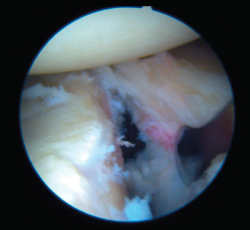

Bankart associated HSLs are found in a large percentage of cases (71-100%); we must distinguish whether the lesion is an impingement lesion or not(33) or - if GT measurement has been used to globally assess the humeral and glenoid bone deficit - we must determine whether the lesion is on-track or off-track.

In the case of an impingement or off-track lesion, the risk of relapse increases considerably(33); in these cases the required surgical manoeuvre should convert the HSL into an on-track lesion again or into a non-impingement lesion. The remplissage technique has been successfully used for this purpose(64) and involves fixation of the posterior capsule and part of the infraspinatus tendon (capsulotenodesis) to the bone defect of the humeral head. Connolly et al.(65) proposed this technique as an open procedure four decades ago, though it was Wolf in 2004 who first described the arthroscopic technique as a modification of the open procedure. Many authors have reported good outcomes combining arthroscopic Bankart repair with remplissage. Wolf et al.(66) reported their findings after up to 10 years of follow-up, with the recording of recurrence in only two out of 45 patients (4.4%). Boileau et al.(61) used this procedure in 47 of 459 shoulders, and only one shoulder (2.1%) suffered recurrent instability. Recent systematic reviews have found the overall recurrence rate after combining both techniques to range from 3.4% to 5.4%, without important joint balance restrictions(67,68). As an undesired effect, the technique may produce a certain decrease in mobility, especially referred to external rotation, though it considerably lessens the instability recurrence rate(61).